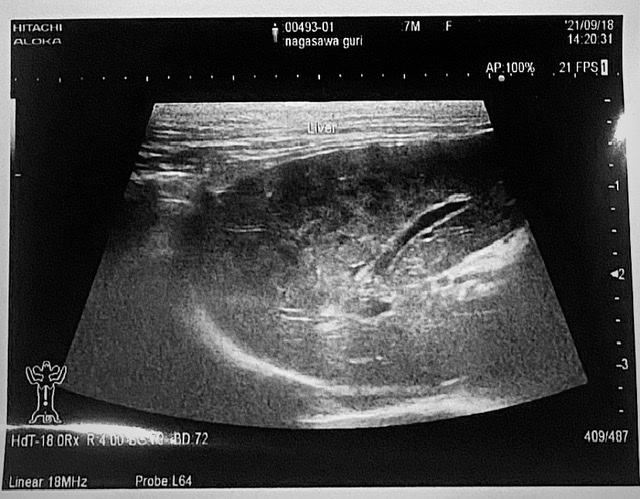

・2021年9月18日

避妊手術前に健康診断を受診。月齢より体重が少ないのと、肝臓の数値があまり良くないとのことで血液検査の結果待ち。

超音波検査後、肝臓にもやがあるのが気になると医師に告げられる。炎症性か腫瘍性か不明との診断を受け、薬で2〜3週間ほど様子見。